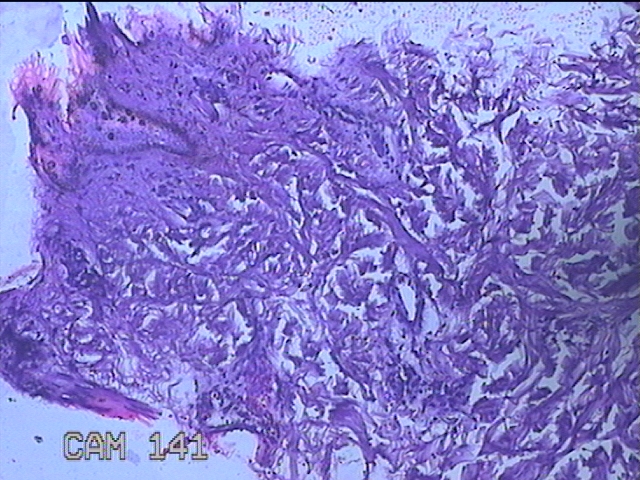

左侧臀部结节

性别

男

年龄

40岁

临床诊断

皮下结节

一般病史

发现左侧臀部结节1年余。

标本名称

大体所见

灰白粉红色组织1.3x0.8x0.3cm一块,表面带梭形皮肤1.3x0.8cm,皮下见结节1.3x1x0.7cm一个,切开结节呈实性,切面灰白粉红色,质软。